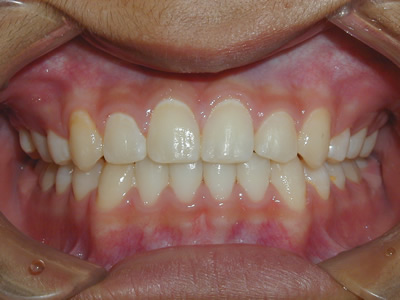

永久歯に交換するためのスペース不足による前歯のガタガタで、取り外しができる拡大床にて上下顎の幅を拡大した後、上顎の前歯をマルチブラケット装置で並べました。治療の期間は1年9か月でした。

初診時

終了時